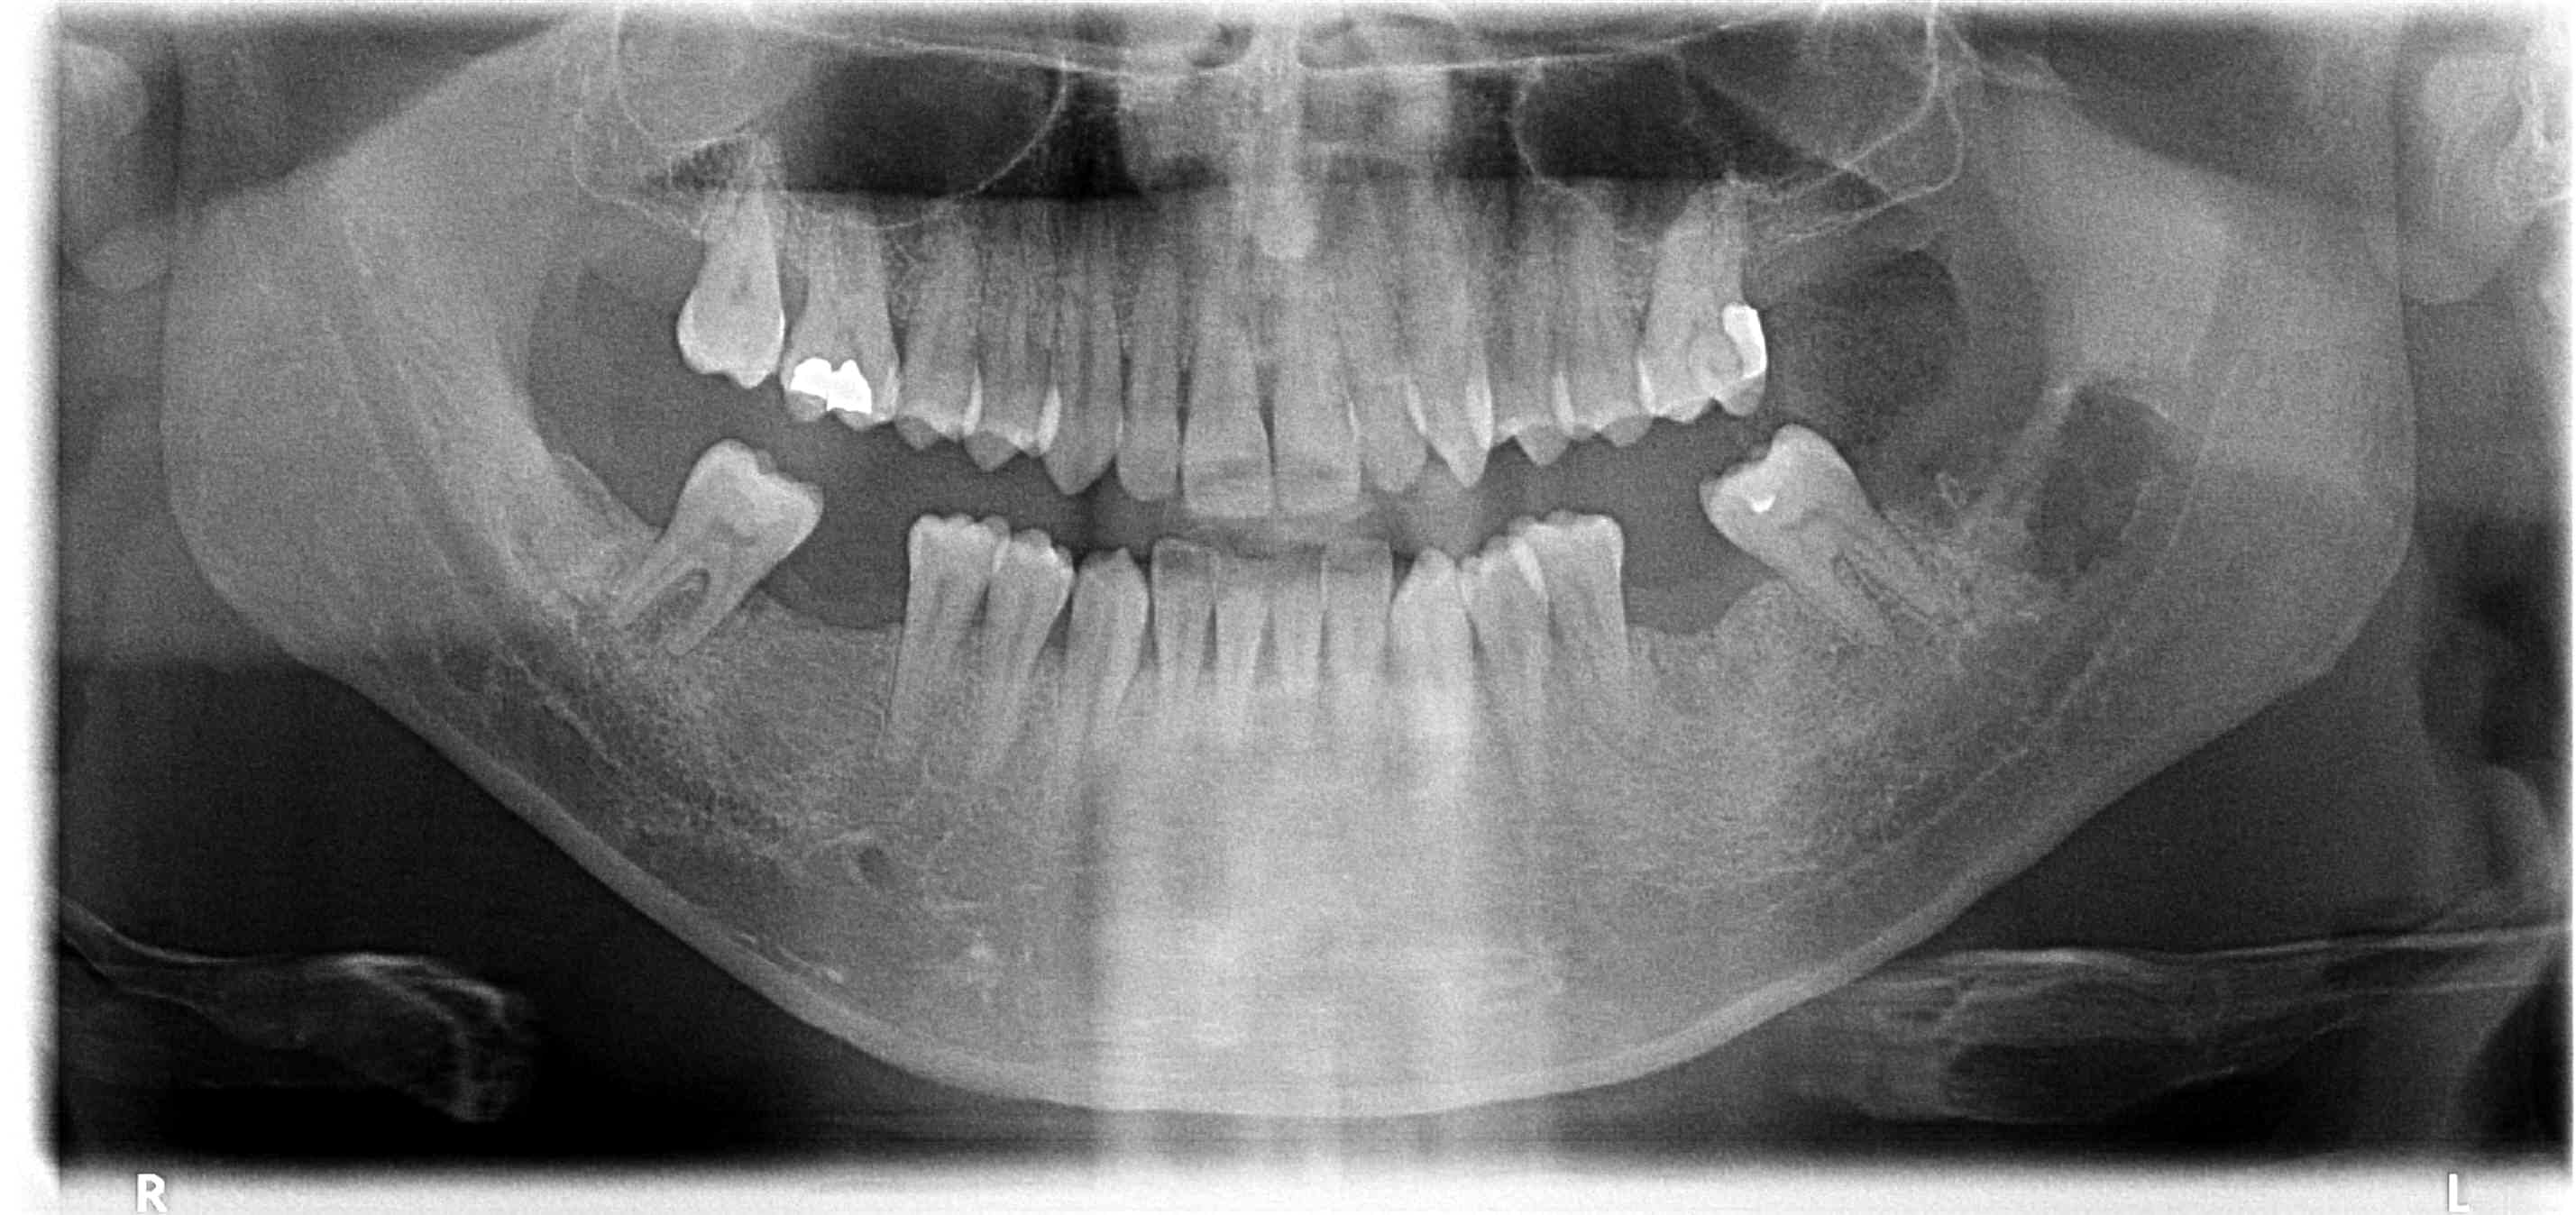

La première pano est celle d'il y a un an, la deuxième, celle du jour après exo de 38.

Après avoir essayé en vain de joindre le patient pour avoir des nouvelles, n'ayant aucun compte rendu de l'hôpital, celui ci appelle pour reprendre RDV. Je prends le téléphone afin d'avoir des nouvelles et il m'annonce tout content que ce n'est pas un cancer, mais que c'est un truc en ... blome d'après les analyses. Je lui dis "améloblastome" (ma grosse inquiétude au départ, image lobulée, situation ... ), il me dit "oui, je suis rassuré", et bien pas moi, mais je n 'ai pas voulu le plomber. J'attends toujours le compte rendu officiel. Apparemment, curetage a été réalisé, et contrôles réguliers ... Je ne sais plus quoi penser.

Revu le patient aujourd'hui, ça semble pas vilain, je pensais le pronostic de l'ameloblastome plus méchant que ça.